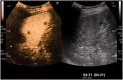

Figure 1.

Melanoma metastases. In this split screen image, the spleen has an inhomogeneous appearance on the low MI grey-scale image (to the readers’ right). On the late-phase CEUS image (readers’ left), contrast has washed out of the metastatic lesions and they are easily visualised within the enhanced splenic parenchyma.